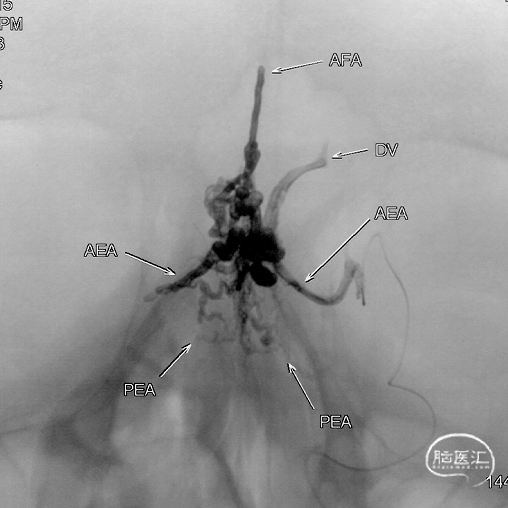

Onyx胶铸型进一步显示了瘘的结构。AFA:镰前动脉;AEA:筛前动脉;PEA:筛后动脉;DV:引流静脉。

通过Marathon微导管注入Onyx 18,胶向瘘口弥散,并弥散至镰前动脉。

停顿后进一步注射Onyx18,此时胶向对侧筛前动脉弥散,直至闭塞瘘口和引流静脉起始端。

最终造影瘘口完全不显影。